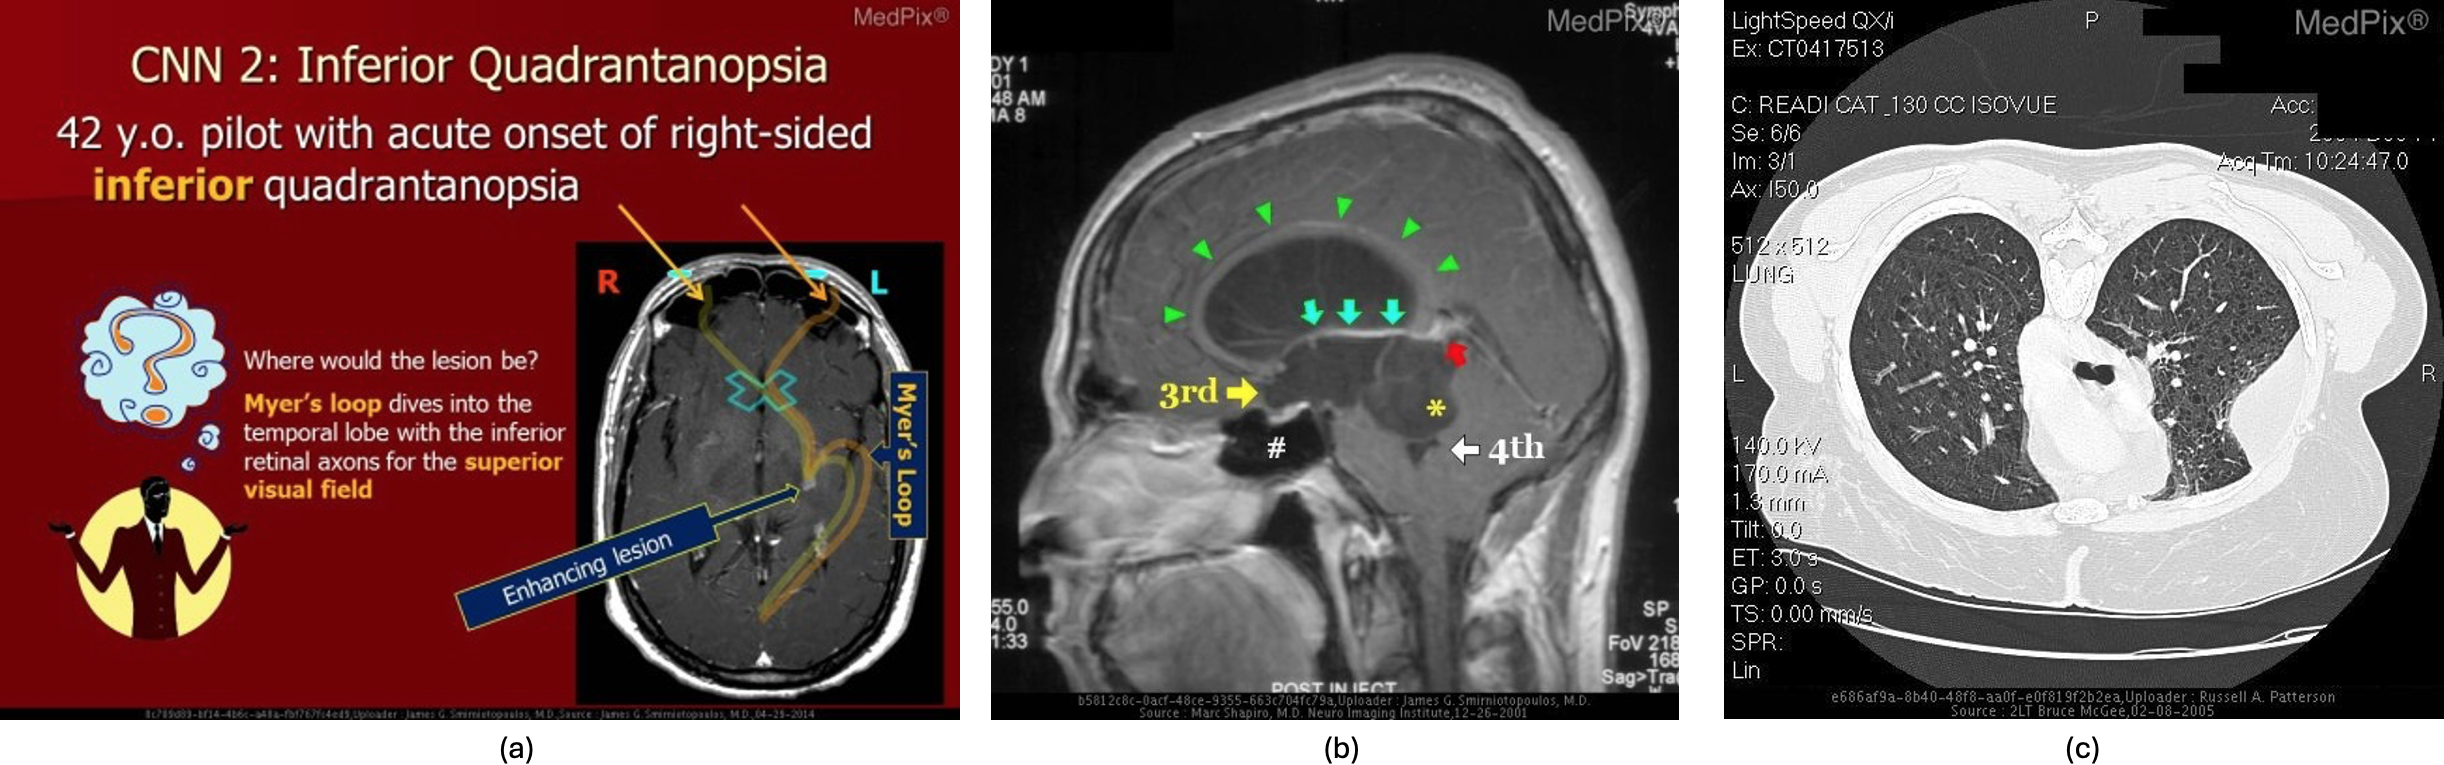

Figure 2: Among the manually removed images there are presentation’s slide (a), manually (b) and automatic annotated images from DICOM viewer (c)

We decided to focus on a part of MedPix® that involves cases related with two diagnostic modalities, namely Computed Tomography (CT), and Magnetic Resonance Imaging (MRI). First of all, the images in the considered split were downloaded via Open-i® 555https://openi.nlm.nih.gov/s: among them, there where some noisy images such as teaching materials or annotated images (Fig. 2) that are inconsistent as input image for training a VLM for which we expect a clear CT or MRI. In particular, this process of curing the data set by removing noisy samples, was performed via manual direct inspection of all the automatically downloaded samples. This was the only non-automated task performed during the data set extraction process; therefore, we refer to our approach as semi-automated. This selection was crucial, because the use of images with artefacts, such as the ones shown in the figure (e.g. symbols, annotations), would not allow a correct visual feature extraction, leading to relevant biases in the classification process of the multimodal model.